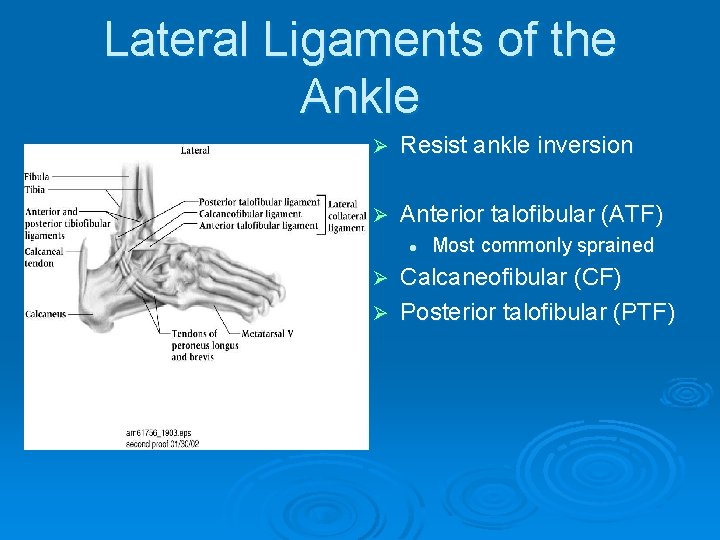

Lateral Ligaments of the Ankle Ø Resist ankle inversion Ø Anterior talofibular (ATF) l Most commonly sprained Calcaneofibular (CF) Ø Posterior talofibular (PTF) Ø